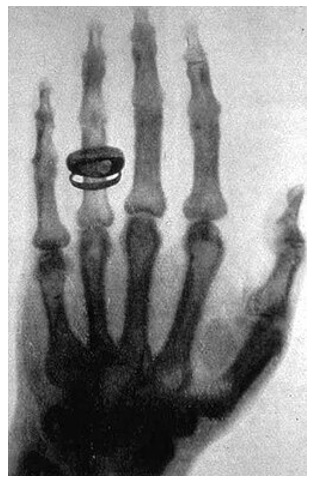

Η Ακτινολογία είναι μια από τις πιο καίριες ειδικότητες της Ιατρικής που τα τελευταία χρόνια, λόγω της εξέλιξης της τεχνολογίας που τη συνοδεύει, έχει αποκτήσει ανεκτίμητη αξία και αποτελεί ουσιαστικό συνδετικό κρίκο στη διάγνωση και διαχείριση των ασθενών. Συνοδεύεται και ενισχύεται από πληθώρα τεχνολογικών εξελίξεων, που είναι εντυπωσιακές αν θυμηθούμε την εποχή που ο κύριος Röntgen απεικόνισε την παλάμη της συζύγου του, με τη βοήθεια των «αόρατων» ακτίνων Χ, 130 χρόνια πριν στις 8/11/1895.